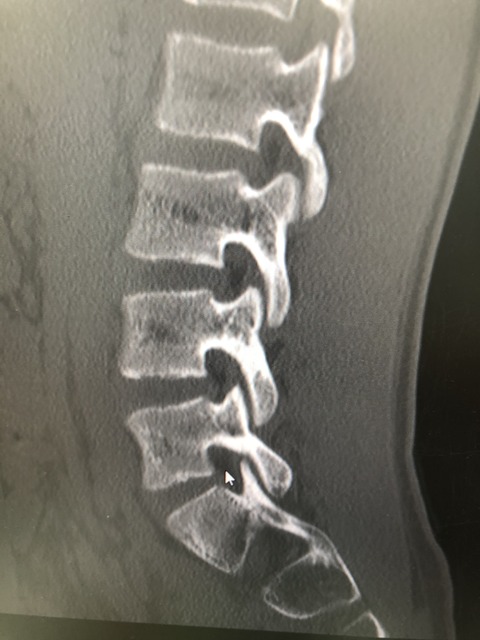

成長期の分離症や、肘、膝の軟骨損傷など難治性が

家での、ストレッチや、

筋トレで、皆さん軽快して行っております

こういう時こそ障害、怪我を

乗り切っていきたいと思います

難治性といわれる腰椎分離症も続々と完治!